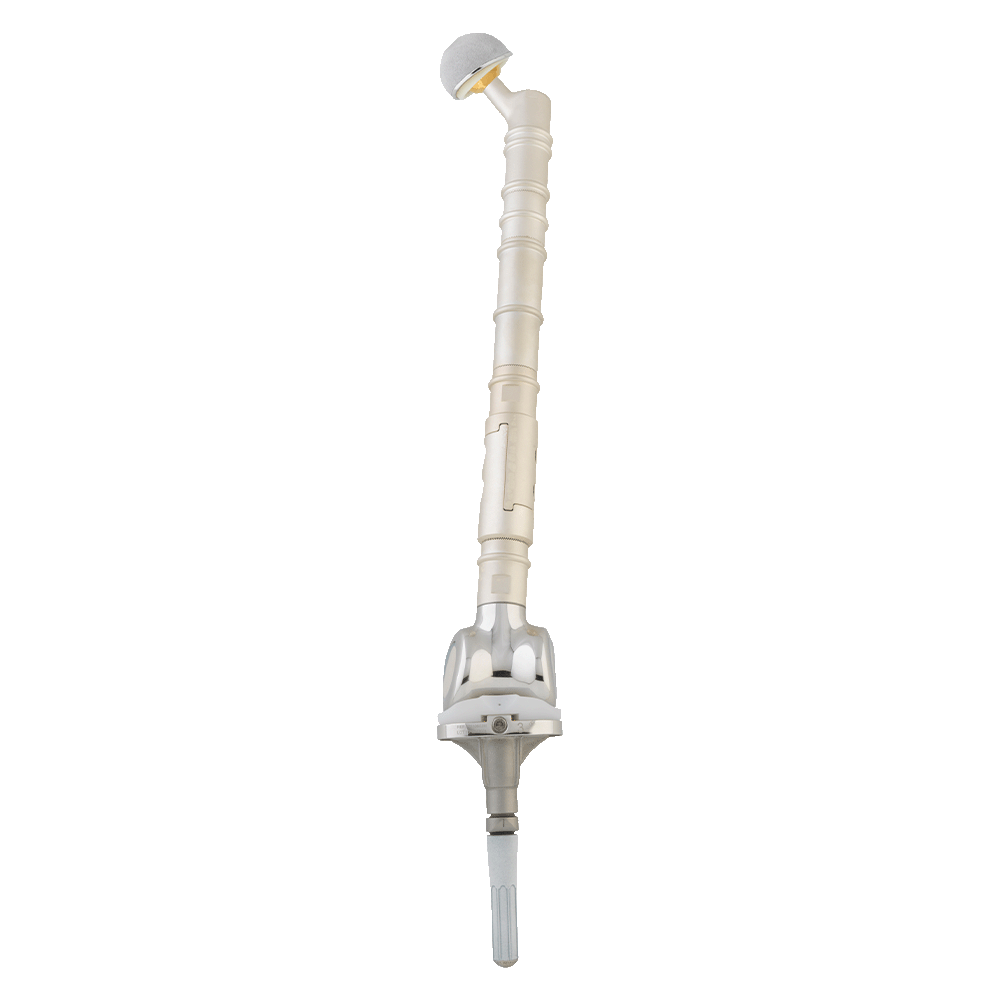

Revêtement Argent

Prévention avancée des infections

Technologie exclusive implantcast, en collaboration avec l’Hôpital Universitaire de Münster

Depuis 2004, Implantcast développe un revêtement à base d’argent appliqué avec succès sur une large gamme de composants du système modulaire MUTARS®.

Ce revêtement a pour objectif principal de réduire le risque d’infection postopératoire et ainsi prolonger la durée de vie des implants.

Avantages du revêtement en argent Implantcast

- Réduction prouvée des taux d’infection

- Libération prolongée d’ions argent pour une protection à long terme

- Barrière contre les biofilms

- Résultats cliniques solides (efficacité démontrée dans plusieurs études)

Technologie

ChezImplantcast France, nous intégrons des évolutions technologiques dans la conception de nos implants orthopédiques, destinés à une utilisation par les chirurgiens conformément aux indications prévues. Titane en impression 3D, revêtement TiN et traitement de surface Argent pour les prothèses massives.